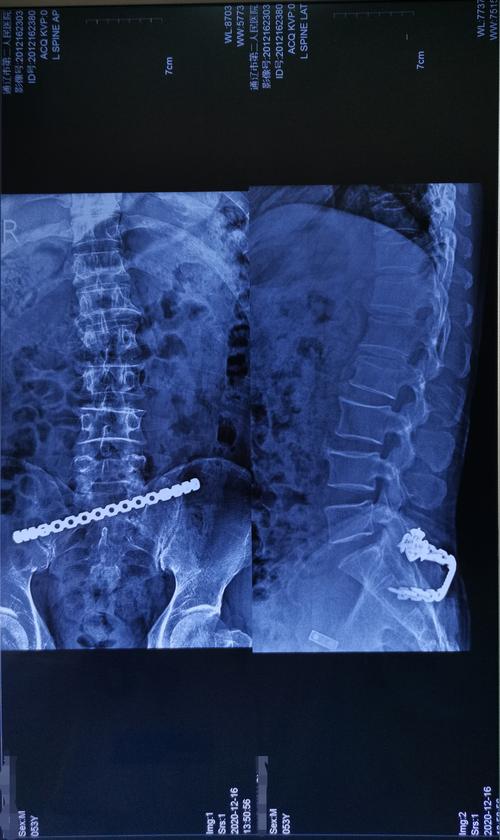

腰椎骨折经皮置钉手术

54岁腰椎压缩性骨折切开复位椎弓根内固定手术一例